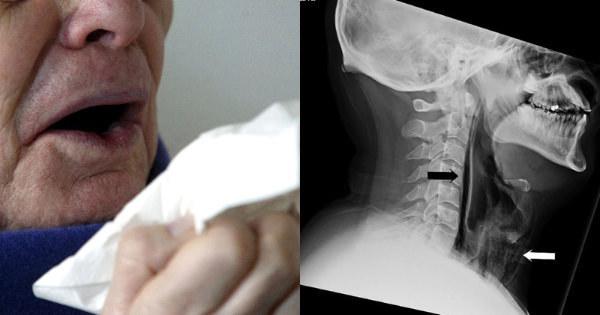

34-Year-Old Man Ruptures His Throat Because He Was Trying To Hold In A Sneeze

Just like your feelings, you shouldn't suppress a sneeze.